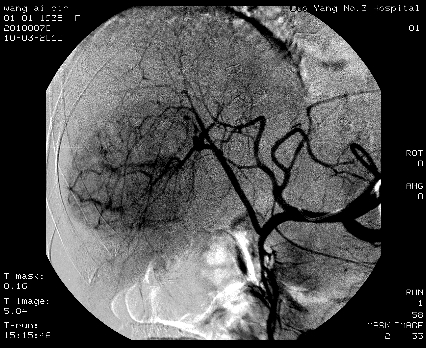

(七)、经皮经肝胃冠状静脉栓塞术

是消化内科开展的另一项治疗肝硬化并发消化道大出血的另一种血管介入技术,该技术通过经皮肤、经肝进入门静脉—胃冠状、胃短静脉—食管、胃底曲张静脉,注入栓塞剂(如无水酒精、弹簧圈),使曲张静脉闭塞,可有效防治出血,明显降低出血机率,疗效显著。可与内镜下曲张静脉套扎术、外科断流术综合运用,提高疗效。